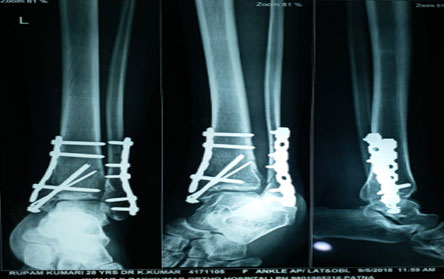

Trauma surgery:

Trauma surgery is a surgical specialty that utilizes both operative and non-operative management to treat traumatic injuries.

The Center of Orthopedics KUMAR ORTHO HOSPITAL ,Patna, offers the entire spectrum of modern orthopedic management, which is effective, patient - friendly & result oriented. In a nutshell, it is one stop treatment for all orthopedic ailments and fractures with emphasis on avoidance of complications, rapid mobilization, decreased period of confinement and an early return to normalcy.